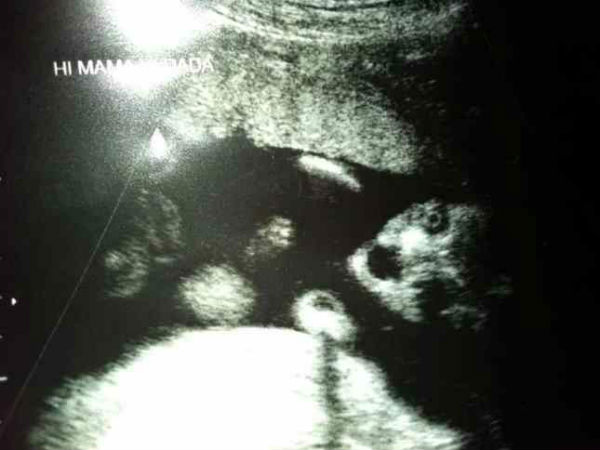

చిత్రం #3 బిడ్డ నిండుగా ఉండడం!

బిడ్డ ఎక్కువ కనిపిస్తుందా? అతను/ఆమె పెద్దగా కనిపించి, శిశువు ప్రపంచం లోకి రావడానికి సన్నద్ధంగా ఉన్నట్టు తెలుస్తుంది!